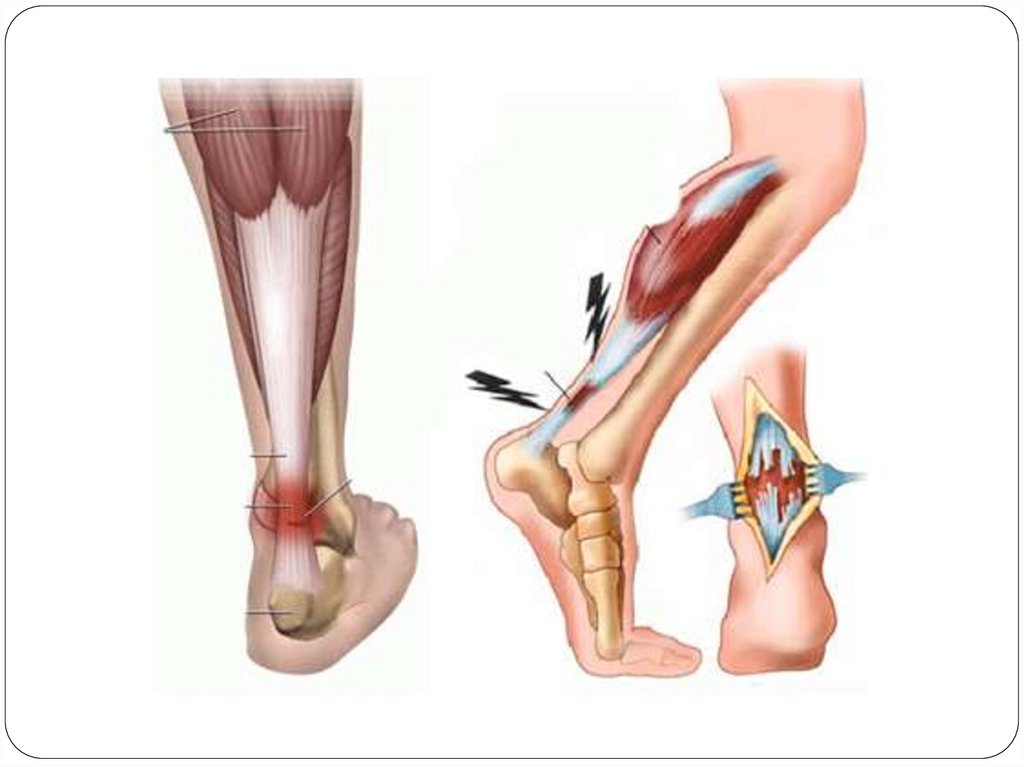

Растяжения (distorsio) и разрывы (rupturae)

– наиболее часто встречаются при повреждении

связок суставов, сухожилий, мышц и

внутренних органов.

Растяжение – механические повреждения

тканей с частичным их разрывом, но при

сохранившейся анатомической непрерывности.

Разрывы – закрытые механические

повреждения мягких тканей или органов с

нарушением их анатомической непрерывности.

Разрывы возникают обычно в результате

действия силы, растягивающей ткань за

пределы ее эластичности при перерастяжении.

17.

Клиника:

боль, припухлость, нарушение функции мышцы

или полное выпадение ее;

дефект в сухожилии или мышце, определяемым

при пальпации;

смещением мышечного брюшка в сторону

неповрежденного прикрепления мышцы.

18.

Первая помощь:

применяются те же мероприятия, что и при

ушибе.

При растяжении -иммобилизация до 3-х недель.

При разрывах – обязательно операция,

восстановление целостности поврежденного

органа с последующей более длительной

иммобилизацией ЛФК, реабилитационные

мероприятия.